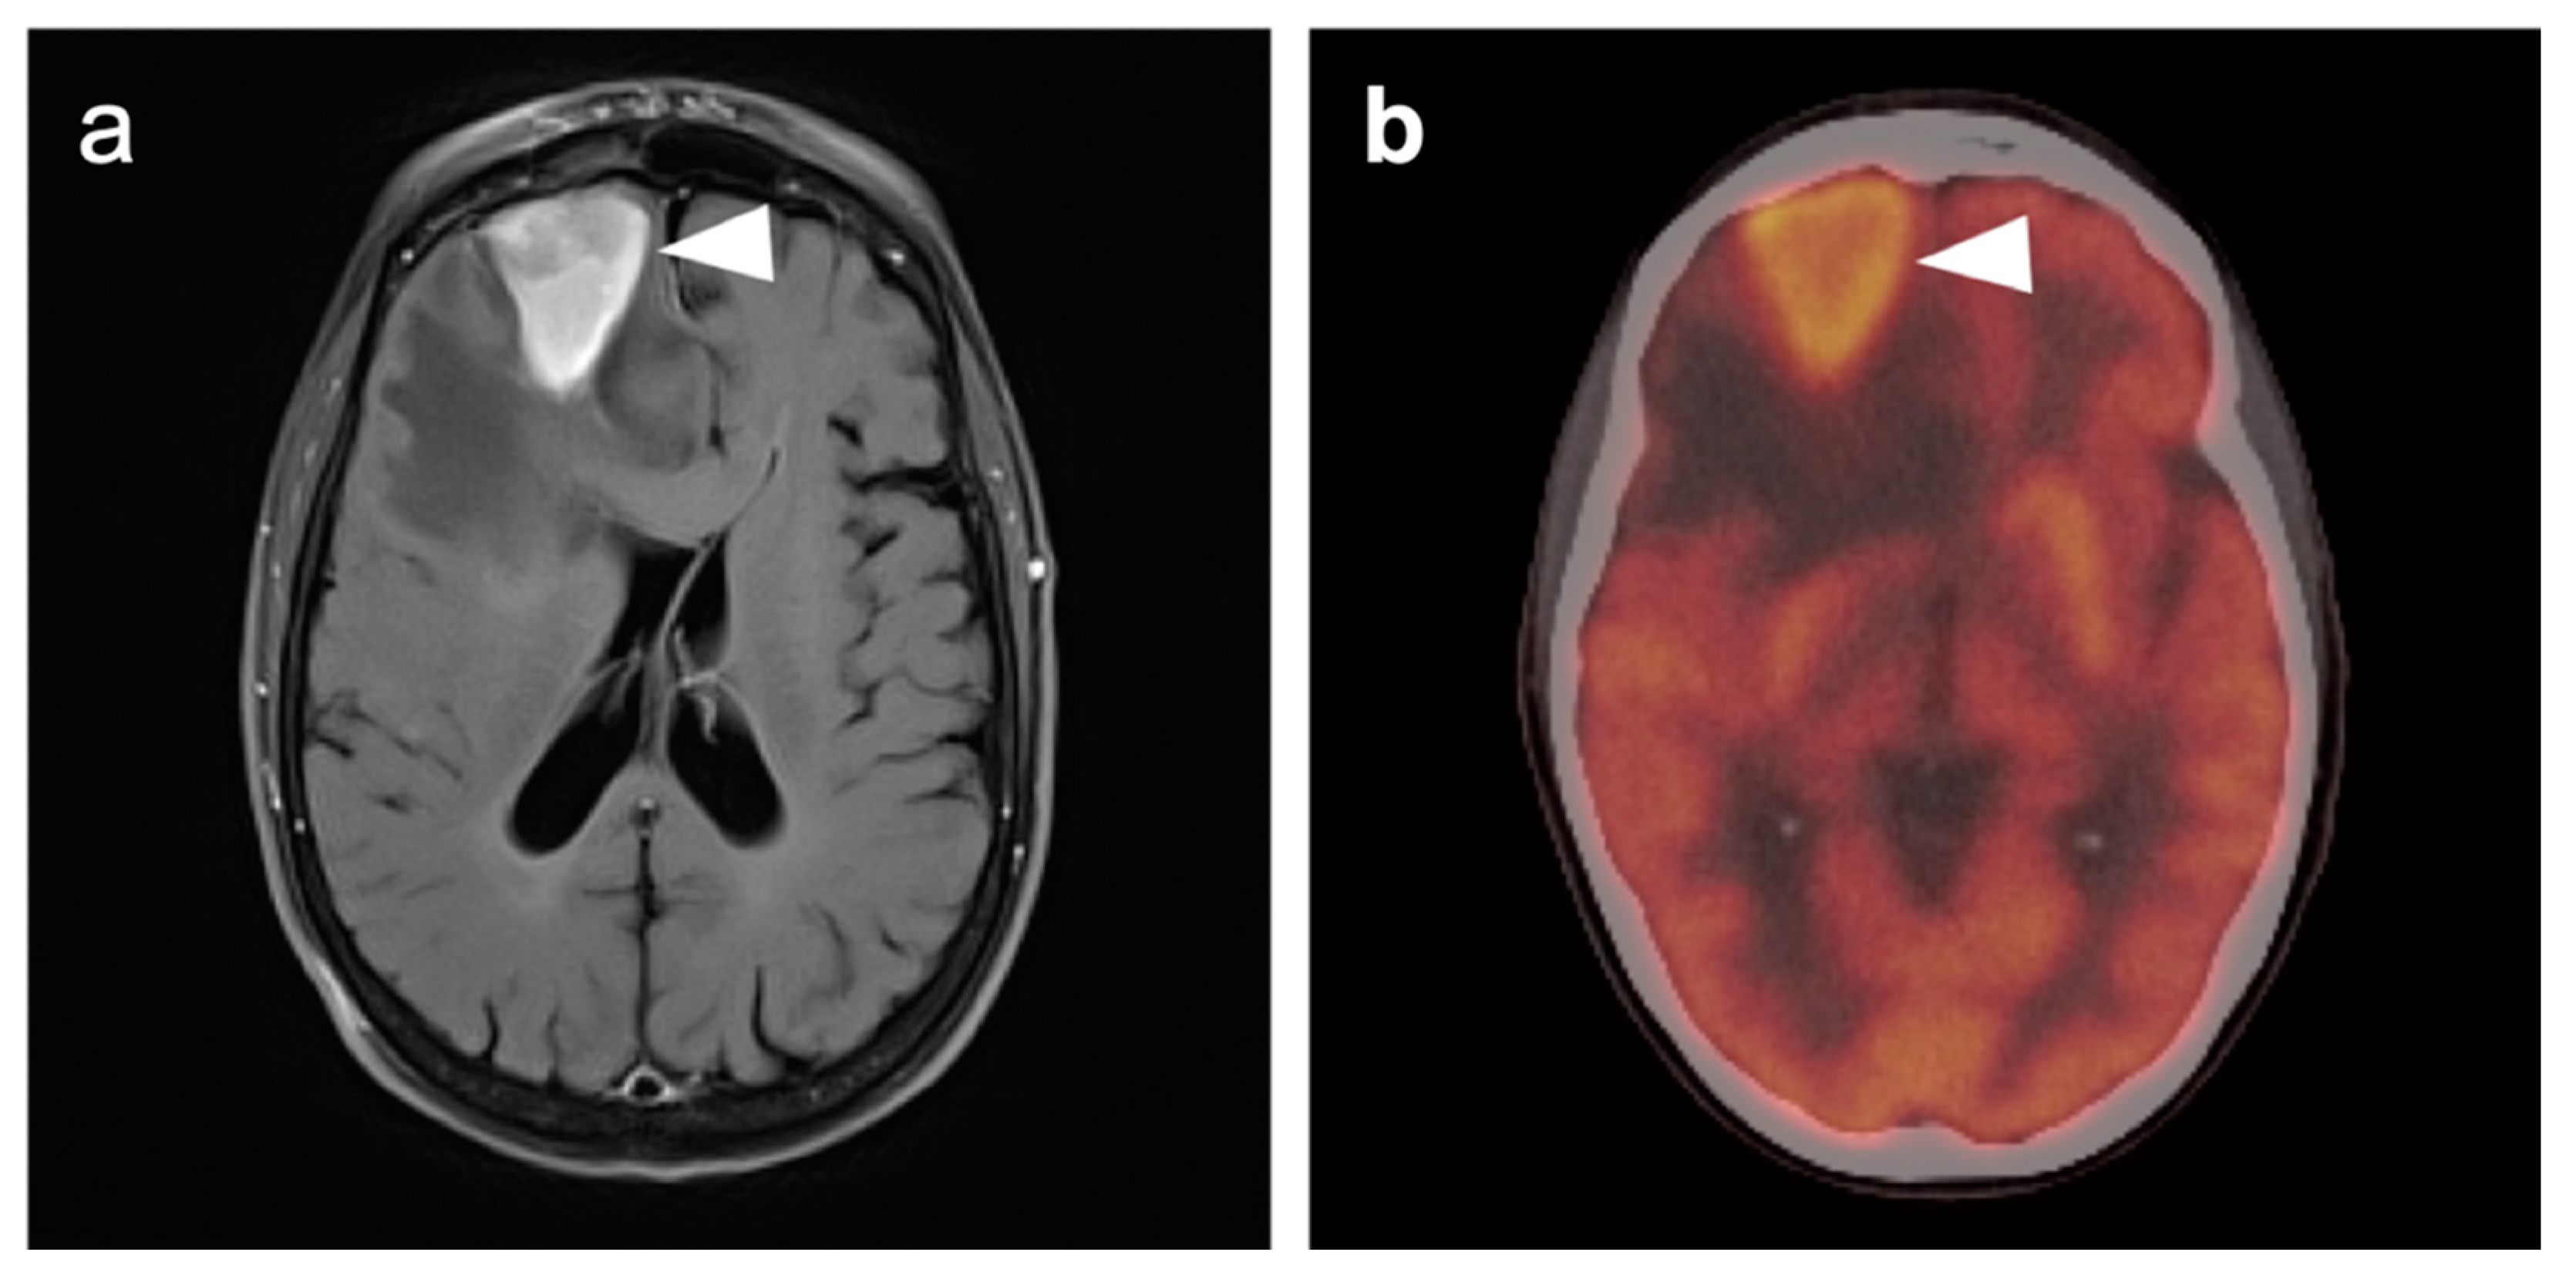

3.4. CNS Lymphoma

3.5. Brain Metastases